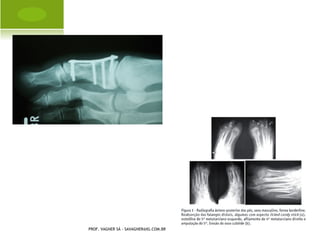

IMAGEM

P OLIDACTILIA

H ÁLUX VALGO A DQUIRIDO

A MPUTAÇÃO C ONGÊNITA P É

S INDACTILIA P É